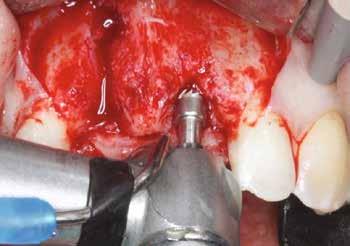

Sebészi technika

Helyi érzéstelenítést végeztünk a műtéti területen artikain és 1:100 000 adrenalin segítségével. A recipiens területet előkészítettük, élesen disszekciót végeztünk, hogy egy izomtapadástól mentes periosteum ágyat képezhessünk. Ettől disztálisan két párhuzamos parakresztális metszést végeztünk egy 15C-s szikepengével, majd a metszéseket egy

2–5. ábra: A metszések és a deepitelizáció. – 6–9. ábra: Félvastag lebeny. – 10. ábra: A nyelezett ínylebeny „bepróbálása”.

horizontális metszéssel kötöttük össze (2–5. ábra). A metszések hosszát és a köztük lévő távolságot minden esetben a lágyszövet augmentációhoz szükséges keratinizált szövet határozza meg. A lebeny deepitelizációját egy 15C-s szikepengével végeztük (6. ábra). Ezt követően félvastag lebenyt preparáltunk (7. ábra). A lebenyt apikálisan, az alapjáról belső, felületes metszéssel felszabadítottuk, hogy passzívan áthelyezhessük és rögzíthessük, feszülés nélkül. Meziális irányba 180 fokkal átforgattuk (8–9. ábra). A meziális papillát alagúttechnikával (tunnelling technique) készítettük elő a graft befogadására (10. ábra). Az így kialakított lebenyt a recipiens ágyban rögzítettük az újonnan kialakított vesztibulum alapjánál 5-0 nem felszívódó PTFE (Coreflon, IMPLACORE) varratokkal. A graftot behajtottuk az ínyszél alá és meziális oldalon rögzítettük PTFE varratokkal (11–14. ábra) A műtétet követően napi kétszeri, 0,12%-os klórhexidin tartalmú szájvízzel történő öblögetést javasoltunk a páciensnek, két héten keresztül. Gyulladáscsökkentésre 8 óránként 400 mg Ibuprofént javasoltunk, három napon keresztül. A páciens elmondása szerint sem fájdalmat, sem különösebb diszkomfortot nem tapasztalt. Ezt követően, további 4 héten keresztül, 0,2%-os klórhexidin tartalmú szájvízzel történő öblögetést javasoltunk a betegnek és instruáltuk, hogy lehetőleg ne mossa fogkefével az érintett területet. A varratokat egy héttel később távolítottuk el. A donor és a recipiens terület – 10 nappal a műtétet követően – kiválóan gyógyult (15–16. ábra). Az ezt követő kontrollokat a következő időpontokban ejtettük meg: kettő, illetve négy héttel a műtét után, majd három, hat és tizenkét hónappal később, ezt követően pedig félévente (17–20. ábra). Minden kontroll alkalmával professzionális fenntartó kezelést végeztünk a területen.